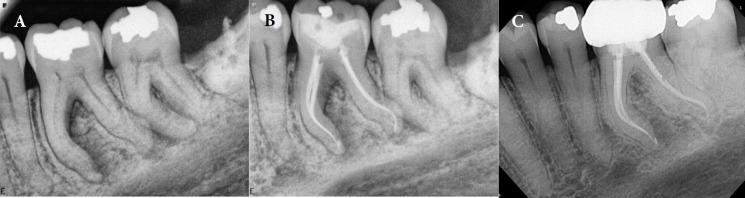

The single-cone technique, also known as the hydraulic condensation technique, is widely employed in endodontics. However, the aforementioned method is presented with certain limitations; specifically concerning the coronal seal and the adaptation of the coronal third of a master gutta-percha (GP) with a round cross-section to the coronal dentinal walls of root canals with semi-round or oval cross-sections. Through two case reports, the current article introduces the coronal vertical condensation (CVC) technique; aiming to enhance GP adaptation to canal walls in similar scenarios. In fact, the coronal vertical condensation technique amalgamates the different aspects of warm vertical condensation and single-cone techniques. In CVC, following the placement of the master GP cone, an electrical heat carrier is inserted immediately a few millimeters apical from the canal orifice to remove the coronal portion of the master GP cone. Subsequently, a hand plugger is used to condense GP in the vertical dimension, and the coronal space is backfilled using melted GP. The implementation of CVC technique has demonstrated an improved coronal adaptation of GP with canal walls. The stated technique seems beneficial; especially in the obturation of severely curved canals or root canals with a final preparation shape of variable taper.

单锥技术,也称为液压加压技术,在牙髓病学中被广泛应用。然而,上述方法存在一定局限性;具体而言,涉及冠部封闭以及圆形横截面的主牙胶尖(GP)冠部三分之一与半圆形或椭圆形横截面根管的冠部牙本质壁的贴合。通过两个病例报告,本文介绍了冠部垂直加压(CVC)技术;旨在在类似情况下增强牙胶尖与根管壁的贴合度。事实上,冠部垂直加压技术融合了热垂直加压和单锥技术的不同方面。在CVC技术中,放置主牙胶尖后,将电热载体立即插入距根管口几毫米的根尖处,以去除主牙胶尖的冠部部分。随后,使用手动充填器在垂直方向上加压牙胶尖,并用熔化的牙胶尖回填冠部空间。CVC技术的应用已证明牙胶尖与根管壁的冠部贴合度有所提高。所述技术似乎有益;特别是在充填严重弯曲的根管或最终预备形态为可变锥度的根管时。